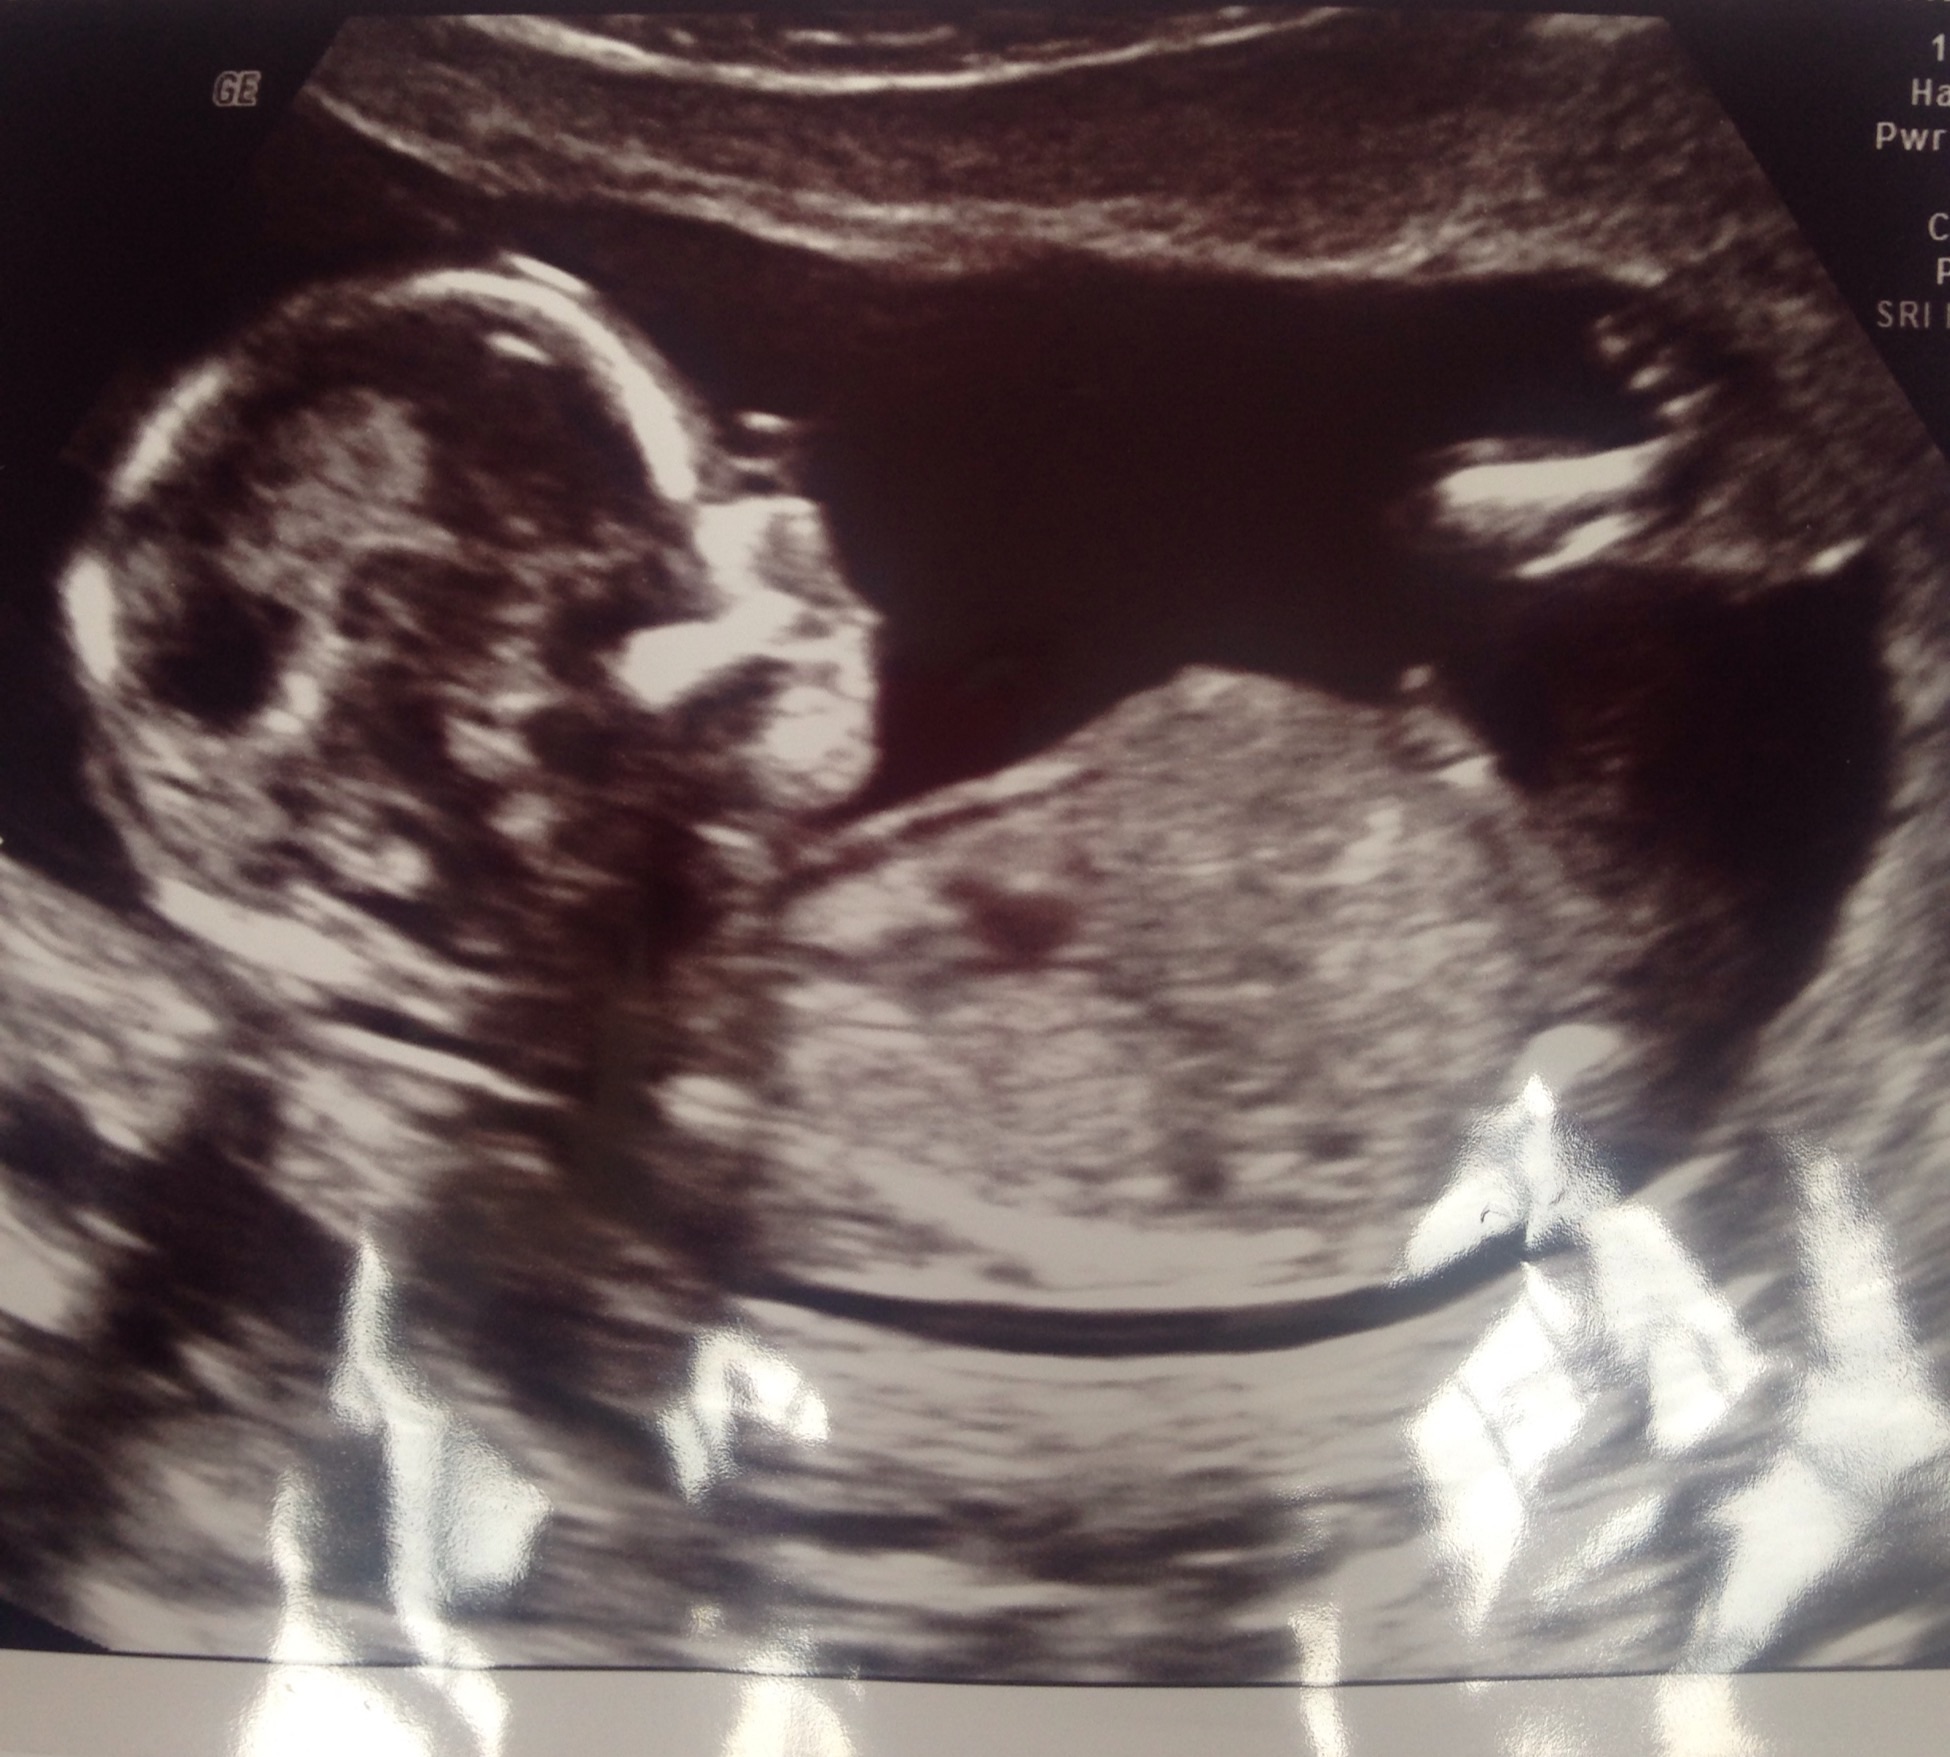

Confirmed boy but slight doubt!?

Hi all 😊 I had a gender scan at 15 + 3 and was told boy. The only reason I'm slightly doubtful is first she said 'hang in its got the cord between its legs' wiggled the devise and said 'yep it's a boy' Just a tad concerned that it is the cord. I don't want to start buying things until I get a second opinion at my 20 weeks scan but thought I'd post the pics to see what you all thought. Also I can't tell whether the potty shot is between the legs or side on 😕 Thank you 😊 xxx

Attachment 26076